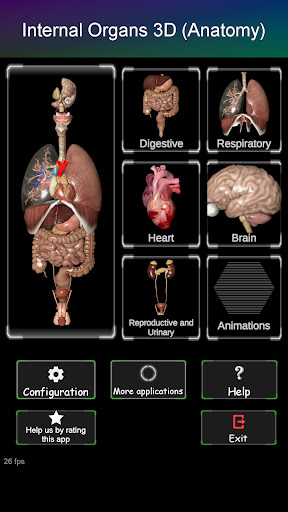

Показує 3D анатомічну модель основні органи людського тіла та опис кожного з них.

Що в додатку?

* Травна система, включаючи шлунок, тонку кишку, товсту кишку та анімацію цієї системи.

* Дихальна система, яка включає трахею, бронхи, легені та анімацію цієї системи.

* Репродуктивна система, яка включає чоловічі та жіночі репродуктивні органи.

* Мозок, який включає головний мозок, мозочок і стовбур мозку.

* Серце, що включає передсердя, шлуночки, аорту і одушевлення цього органу.

Особливості:

* Легкий доступ і навігація (масштабування, 3D-обертання).

* Приховати або показати інформацію.

* Порівняйте чоловічі та жіночі органи.

* Описи кожного органу.

Ця програма розроблена, щоб доповнити вивчення анатомії в різних освітніх, медичних і культурних умовах.

Практична, корисна та цінна анатомічна інформація у вас під рукою.

Завантажте програму сьогодні та вивчайте анатомію в інтерактивному режимі!